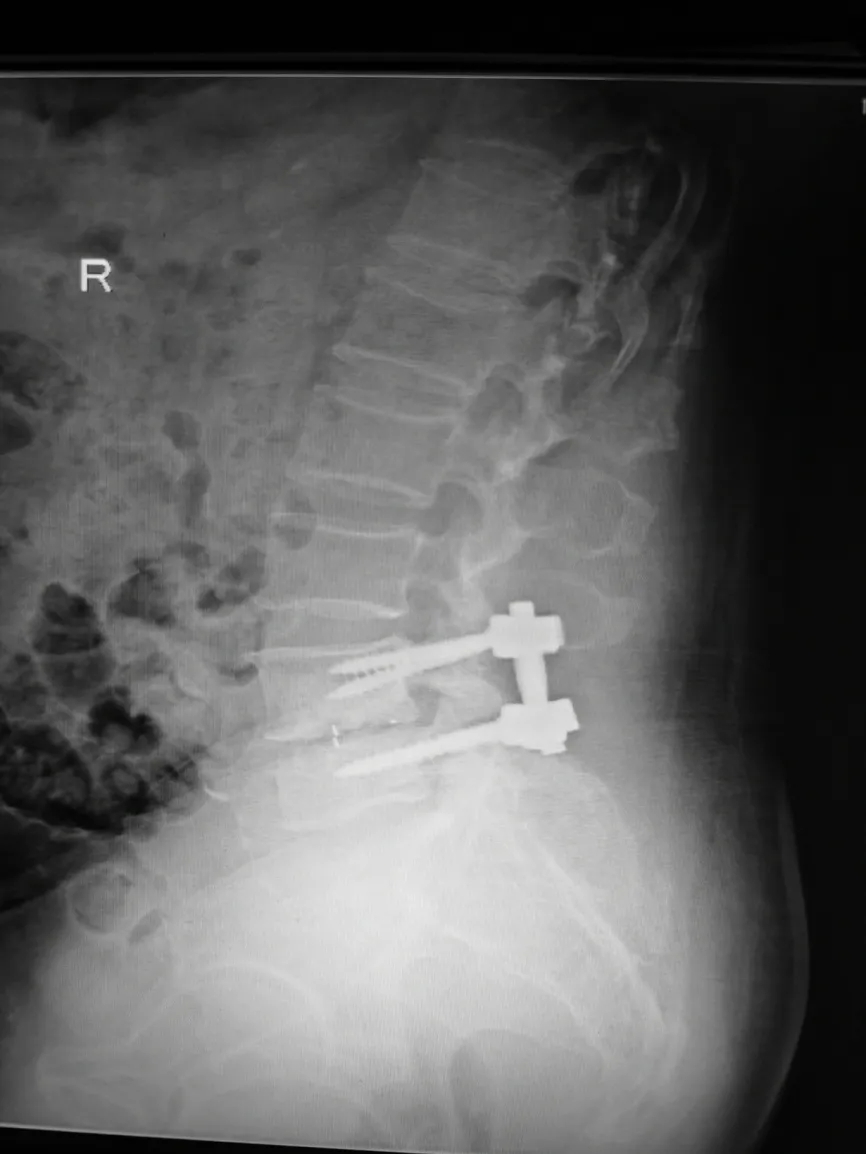

腰椎内固定术后影像:CT可见椎体多个低密度灶。

▲X光片